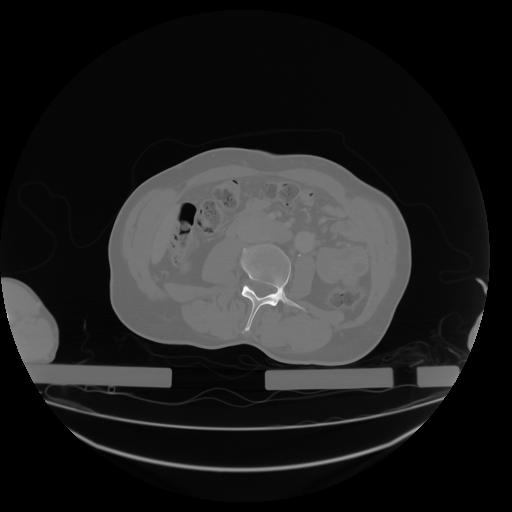

27 CUERPO,CE,Axial,3.0,CUERPO,,